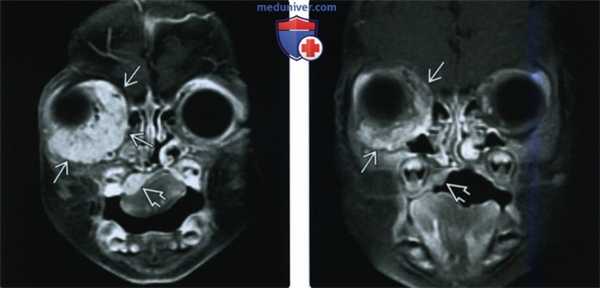

(Слева) При аксиальной МРТ Т1ВИ С+ FS у четырехмесячной девочки с синдромом PHACES в правом околоушном пространстве, задненижних отделах правой глазницы, правой щеке, носу, внутреннем слуховом канале и в области правого мостомозжечкового угла визуализируются множественные гемангиомы, накапливающие контраст. Обратите также внимание на гипоплазию правой гемисферы мозжечка.

(Справа) При аксиальной КТ с КУ у семимесячного ребенка с опухолью носа визуализируется объемное образование, интенсивно накапливающее контраст, и вызывающее окклюзию преддверия носа слева. Все характеристики и расположение этого образования типичны для МГ.

(Слева) При корональной МРТ Т1ВИ С+ FS у двухмесячного ребенка визуализируется крупная МГ, интенсивно накапливающая контраст, находящаяся как внутри, так и снаружи мышечной воронки глазницы; видно также другое объемное образование в области неба справа.

(Справа) При корональной МРТТ1ВИ С+ FS у этого же пациента шесть месяцев спустя после лечения пропранололом с целью предотвращения осложнений со стороны глазницы определяется существенный регресс объемных образований в глазнице и небе.